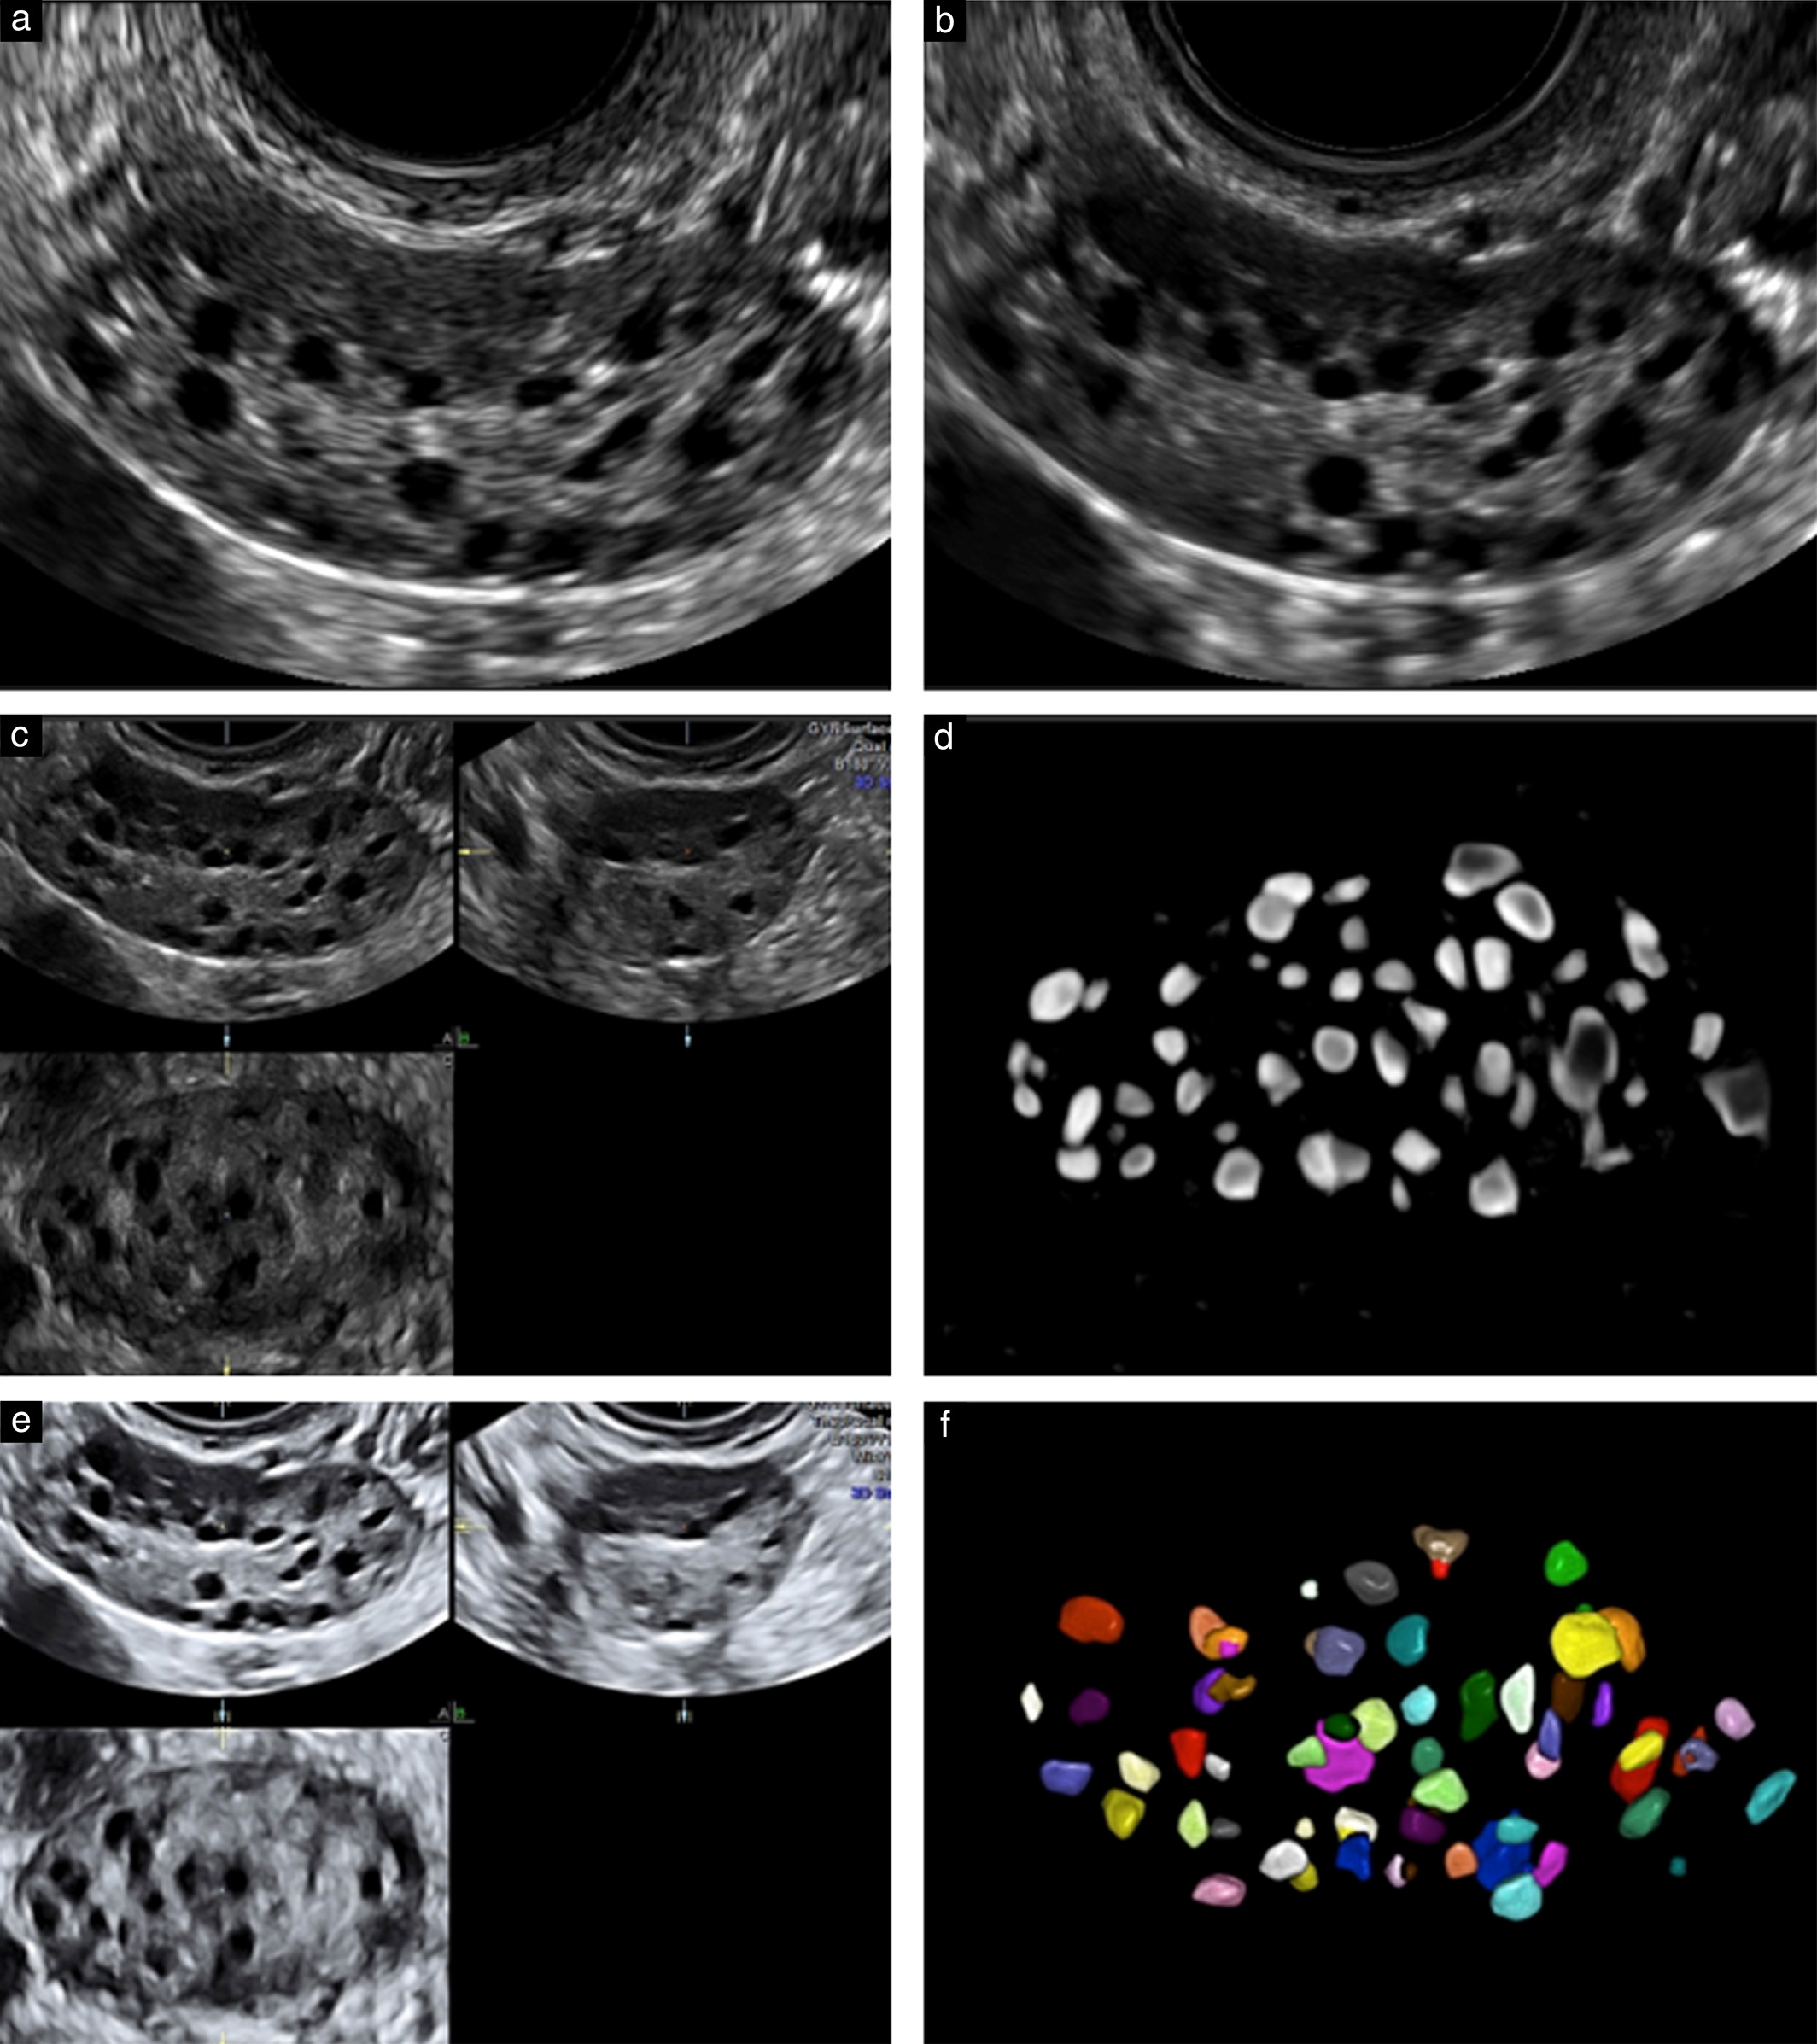

Counting ovarian antral follicles by ultrasound: a practical guide